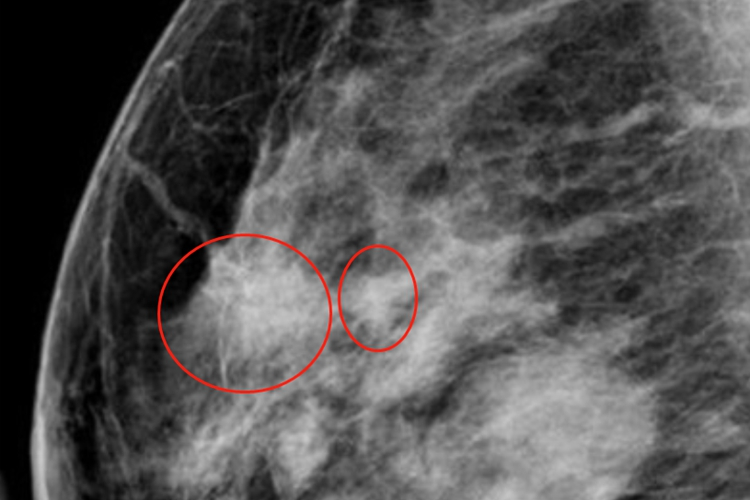

乳腺增生可表现为乳房疼痛、乳房肿块或者结节等,触摸局部质地较硬。乳房疼痛常为胀痛或刺痛,疼痛严重者不可触碰,甚至影响日常生活及工作,疼痛以乳房肿块处为主。乳房肿块发于单侧或双侧乳房内,单个或多个,形状有片块状、结节状等,乳房可有明显肿大的情况。影像学检查可有弥漫性密度增高,尤其是乳头下方,呈不均匀的片状影,边缘模糊。